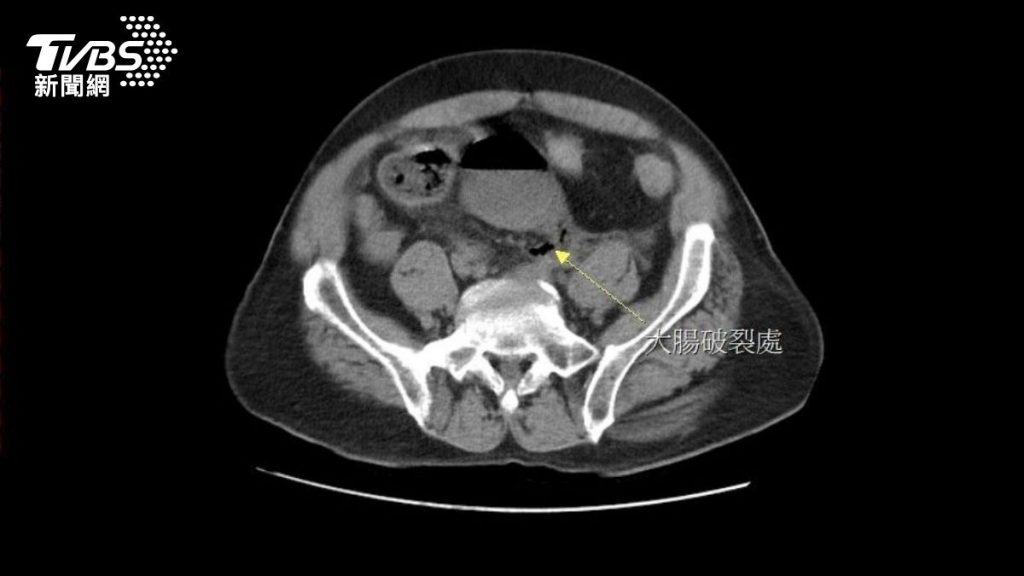

近日,黄男因连续3天无法解便而自行灌肠,却发现没有效果,于是改用更长的管子,把泻药送入直肠深处灌肠,没想到竟突然引发剧痛,被家人紧急送至大千综合医院急诊,经安排电脑断层扫描后赫然发现,在直肠上端处有一个巨大的破洞,粪水随着破洞流进腹腔,引发严重的腹膜炎。

外科部主任冯启彦紧急进行腹腔镜手术,术中发现直肠上端靠近乙状结肠的转弯处,有一个直径2公分的破洞,研判应是太用力灌肠造成的肠道破裂。而这个破洞也让大量的宿便流进腹腔,才会引发严重的腹膜炎。所幸,病人在接受手术后顺利康复,也吓得直呼“再也不敢自己随意灌肠了!”